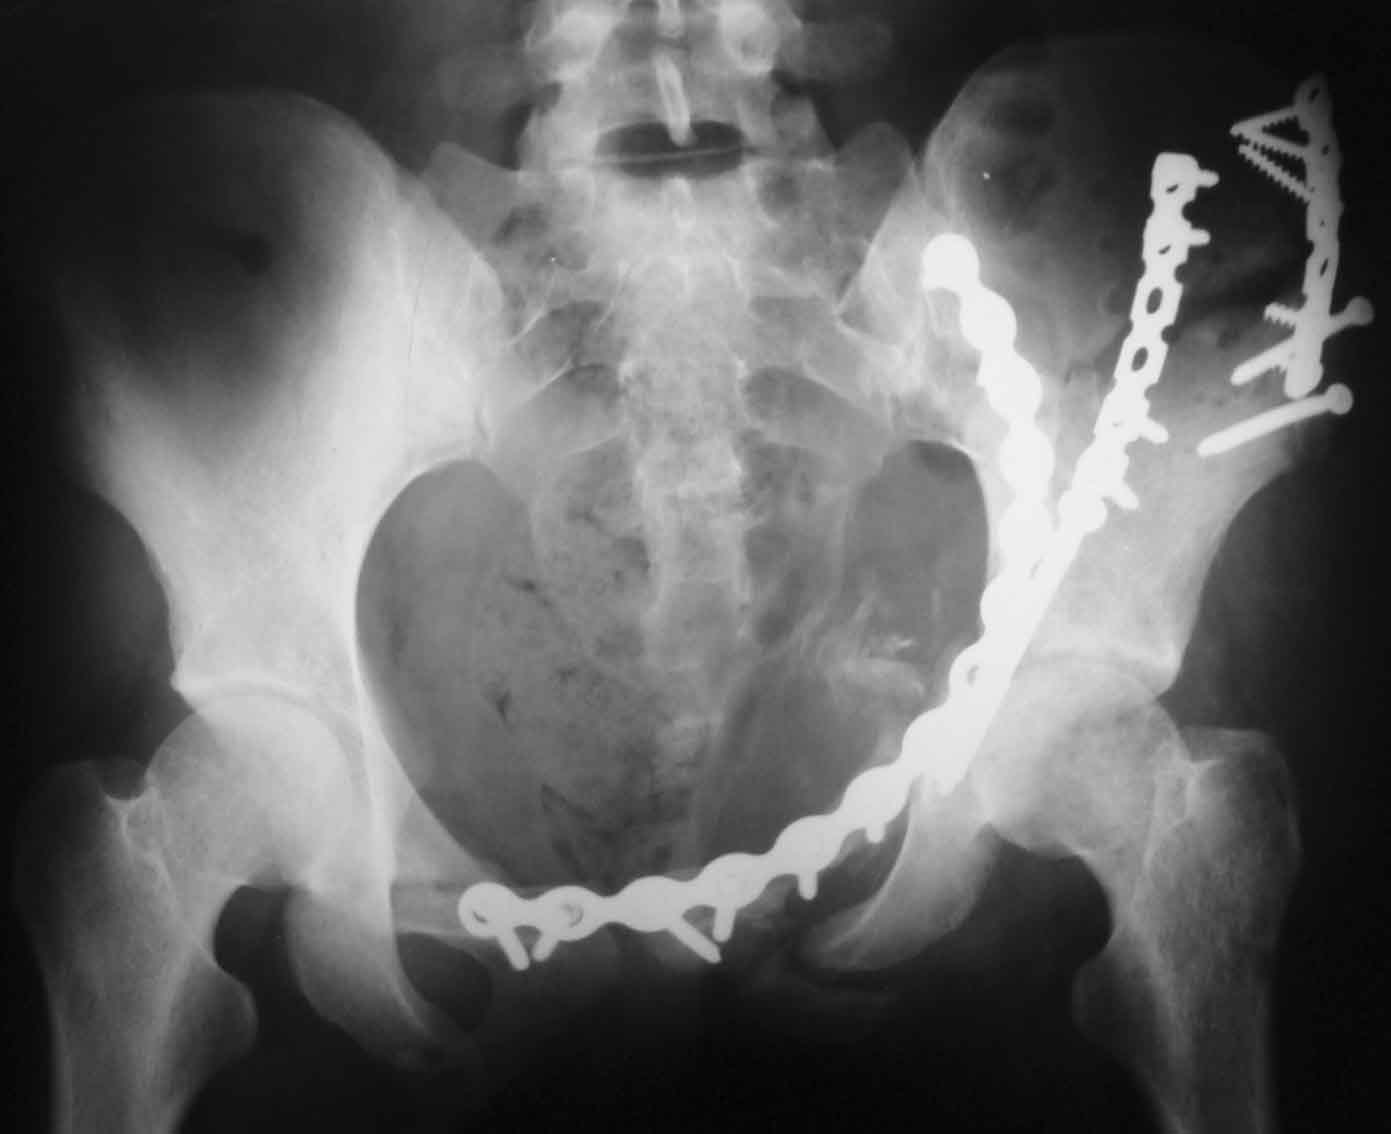

[Ortho] Рентгенограммы после операции

Прямая проекция